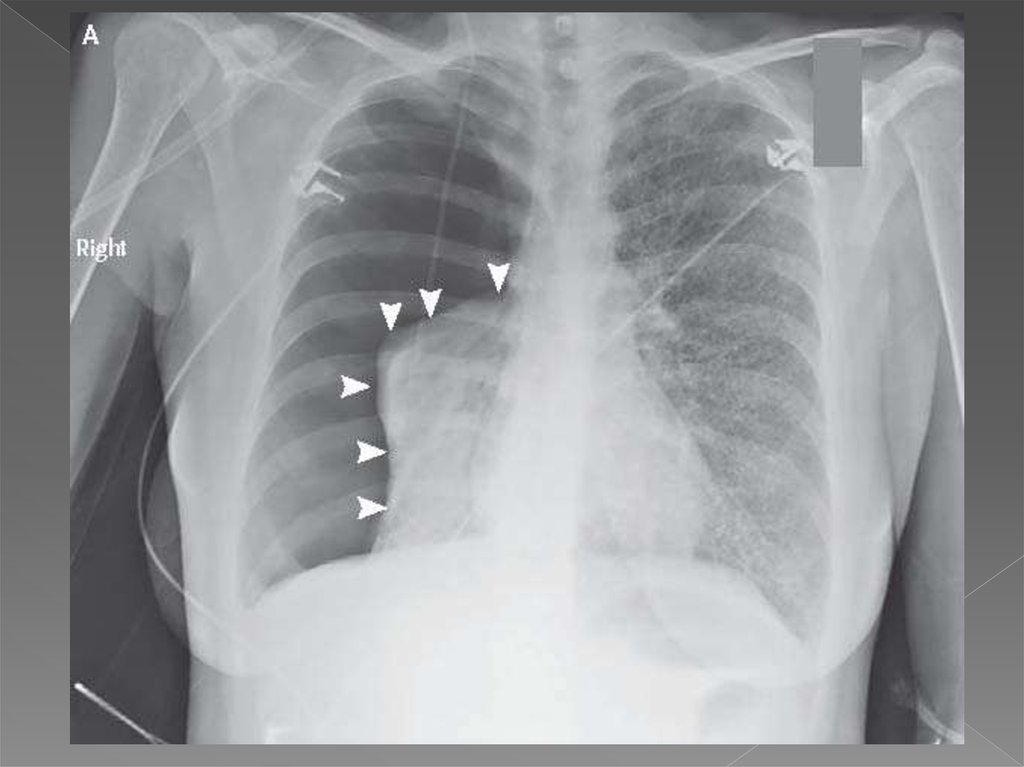

Пневмоторакс Легких Фото 119 фото